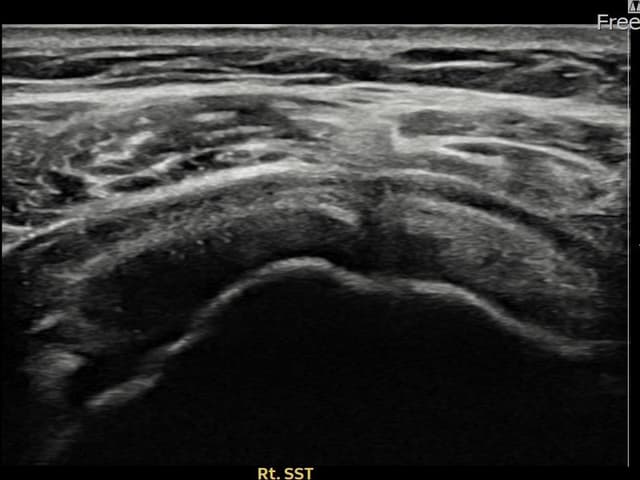

[촬영시기:25.08.20~25.11.18]

[어깨인대 축소봉합술] 좌측 어깨 통증으로 팔을 옆으로 들어올리기 어려워 내원하셨습니다.